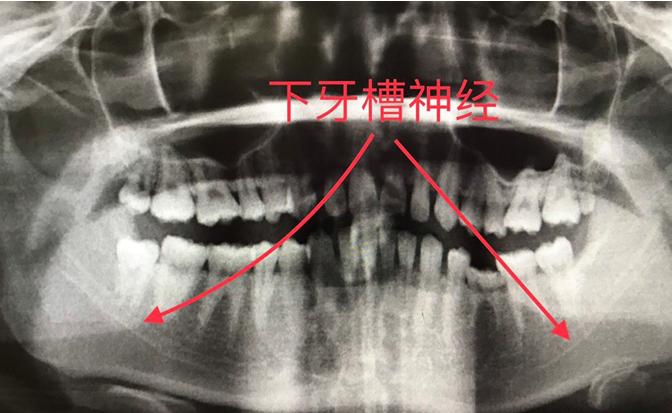

发生嘴唇麻木问题的根本就是下颌阻生齿拔除引起牙槽神经损伤

1. 智齿位置与下牙槽神经距离过近 2. 医生拔牙方式不当,过于鲁莽损伤神经 3. 智齿出现断根问题

由于我们的牙龈处遍布神经,智齿的形态又千奇百状,很少有人的智齿能长的端端正正,很多智齿甚至是贴着神经的边界线长的,所以智齿的拔除,很有可能会伤到神经,在发现智齿形态不好,距离牙槽神经太近的时候,建议患者先做截冠术。